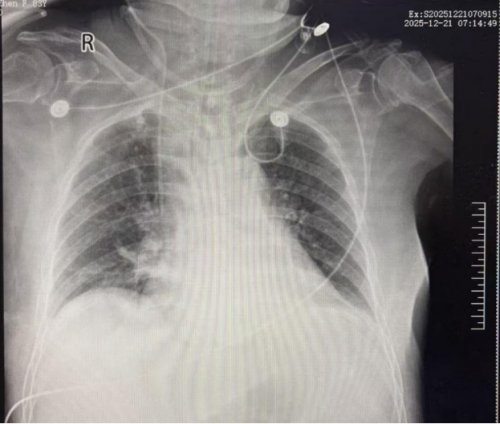

胸部X线:支气管炎,右下肺炎症

2025年12月22日